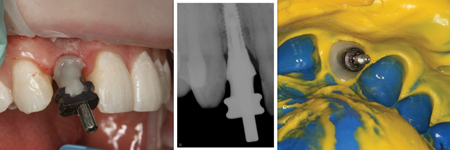

Cementation

On return from the ceramist, the porcelain restoration and abutment were inspected on the die for marginal fit and on the solid model for proper interproximal contacts. An Optragate lip retractor (Ivoclar Vivadent; Amherst, NY) was placed to assist in isolation. The provisional restoration was removed, and the implant interface was cleaned with chlorhexidine to remove any residual debris. The implant abutment was seated using a DuraLay acrylic (Reliance Dental Manufacturing LLC; Alsip, IL) seating jig. (Fig 18) Positive seat was confirmed with a radiograph prior to torquing the abutment to place. (Fig 19) The seated abutment was then torqued to 20Ncm per manufacturer’s instructions. The porcelain restoration was tried into the patient’s mouth and evaluated for fit and esthetics. The patient was then allowed to view and approve the esthetics of his smile in a hand mirror.8

Fig. 18

Fig. 19

The modified open tray style impression coping was screwed into the implant. A check film radiograph was made to confirm accurate and positive seat of the impression coping. A master polyvinyl impression was made with Honigum Pro Light and Heavy impression material (DMG America; Englewood, NJ). Following set of the polyvinyl material, the impression coping was unscrewed and removed as part of the master impression. (Fig. 17) The screw retained provisional was replaced and tightened into position. Teflon tape was placed in the screw access and the facial access hole was filled with matching composite, cured, and polished. A Futar D (Kettenbach; Eschenburg, Germany) stick bite of the teeth in centric occlusion was made and photographed. All records were disinfected and sent to the ceramist accompanied by a completed laboratory prescription and all photographs taken to this point. The ceramist was instructed to use the impression of the approved provisional as a guide for the final shape, size, and contour of the porcelain restoration.